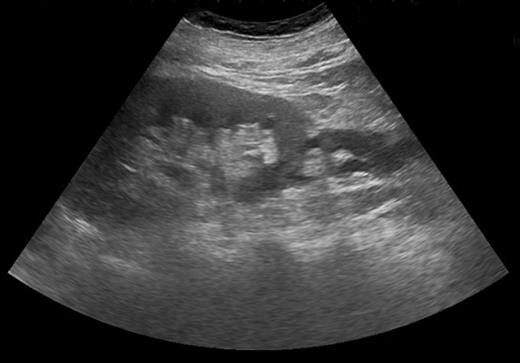

Blood tests revealed a Stage 3 acute kidney injury (baseline renal function was normal) with raised inflammatory markers and elevated PSA compared with baseline (Table 1). A mid-stream urine specimen sent for microscopy, cultures and sensitivities yielded no growth of organisms. A bedside bladder scan revealed a bladder volume of >999 ml, necessitating the insertion of a urethral catheter with a residual volume of 2.4 l, and intravenous antibiotics were commenced. An ultrasound scan (USS) of the urinary tract was performed to evaluate for the presence of hydronephrosis; but while this demonstrated a minor dilatation of the left renal pelvis, it also found a shallow fluid collection around the left kidney extending into the left lateral retroperitoneum, separate from the left psoas muscle (Fig. 1). In the urinary bladder, there was an irregular 4 cm mass on the left posterolateral aspect. In view of the findings, an urgent flexible cystoscopy was performed, revealing a massive median lobe of the prostate protruding up and back into the bladder; the ureteric orifices were not visualized because of this, and the bladder mucosa was normal. The patient subsequently underwent a computed tomography (CT) urogram, which showed bilateral fullness in the pelvicalyceal systems and confirmed a 4.8 × 4.4 × 2.8 cm fluid collection adjacent to the lower pole of the left kidney as detected on the USS, with perinephric stranding. The fluid collection was demonstrated to be extravasated urine on the delayed post-contrast images arising from a defect in the left proximal ureter, and extending down the left paracolic gutter (Figs 2 and 3). The massive prostate was also demonstrable (Fig. 3).

USS demonstrating shallow fluid collection around left kidney.

Severe intractable abdominal pain similar to that attributed to renal colic is the most observed presentation of ureteral rupture [1, 6], and its presence is confirmed on imaging, which may be performed to investigate other causes of pain. CT scan of the urinary tract with a delayed excretory phase of contrast is likely to be the most used means and can determine the presence of extravasation, likely location of rupture and extent of urinoma or abscess formation, as well as the nature of the obstructing lesion. If retrograde ureteral stent placement is to be performed, then pyelography can be performed at the same time to confirm CT findings. Ultrasonography has a limited role for detecting ureteral pathologies but was key here in detecting a perinephric fluid collection and possible bladder mass, which led to further investigations.